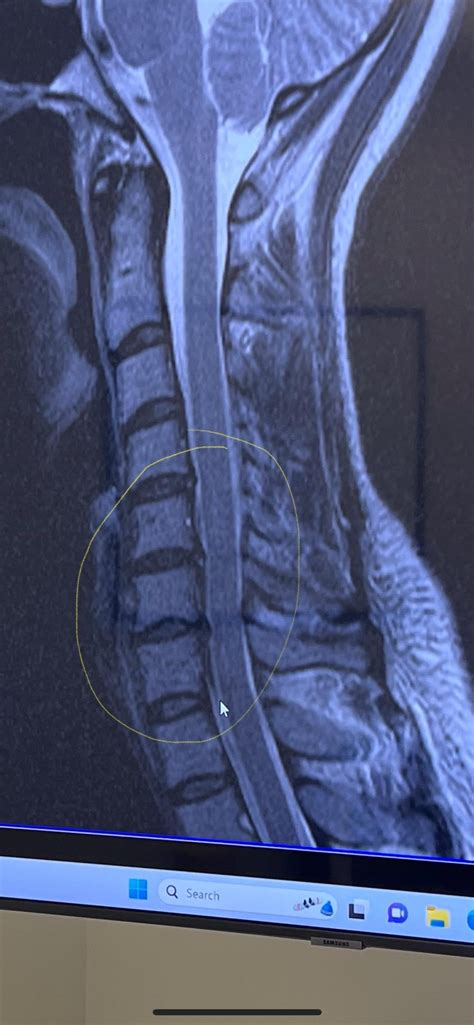

Diagnosing a Bulging Disc in Neck

Diagnosing a bulging disc in the neck typically involves a combination of medical history, physical examination, and diagnostic tests. Your healthcare provider may perform the following steps to diagnose the condition:

• Imaging tests: Ordering diagnostic tests such as X-rays, MRI, or CT scans to visualize the spine and identify the bulging disc.

Based on the findings, your healthcare provider will develop a treatment plan tailored to your specific needs.